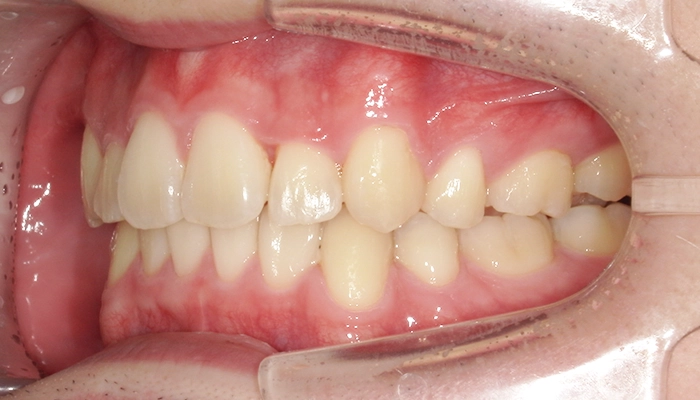

当院にてカウンセリング・検査後、上左右2本、左下1本の計3本と診断させていただき、マウスピース型矯正装置(インビザライン)での治療をご提案しました。

今回の治療では上の両側4番目の歯と、左下の4番目の歯の計3本を抜歯しました。

ワイヤーだと片側抜歯を行うと正中のラインが抜歯した方向へ流れてしまうことがありますが、今回はマウスピース型矯正装置(インビザライン)で行ったため、そのような反作用は生じませんでした。